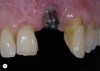

Fig 5. Removal of the restoration further reveals improper implant position from mesial, buccal, lingual, coronal, and angulation perspectives.

Figure 5